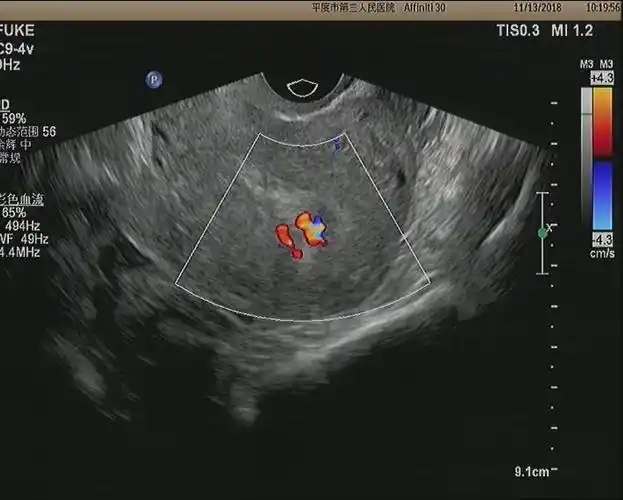

平度市第三人民医院妇科超声检查方法科普小知识